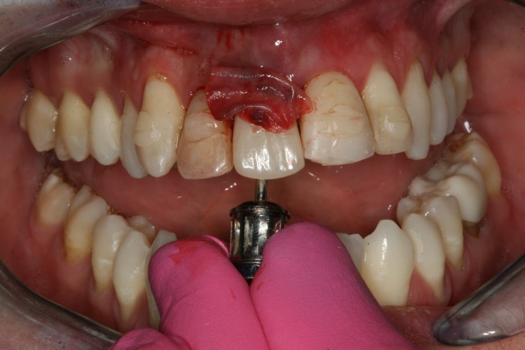

The provisional abutment and treatment crown were fabricated in the laboratory with the digital proposals. Platelet-rich fibrin (PRF) clot technology was incorporated to help with soft- and hard-tissue healing (Figure 19 through Figure 21). The screw-retained provisional and the PRF clot were seated immediately after implant placement (Figure 22 and Figure 23). One 4-0 polytetrafluoroethylene suture was placed to maintain papilla. The teeth immobilization splint was placed for 6 weeks (Figure 24). The rationale for splinting teeth Nos. 6 through 10 was due to noticeable plus-2 mobility of the remaining anterior teeth. The provisional implant crown also was included in the splint.

Fig 21. Platelet-rich fibrin (PRF) clot over the abutment.

Figure 21

Fig 22. Abutment and PMMA positioned with PRF.

Figure 22

Fig 23. Provisional seated into position.